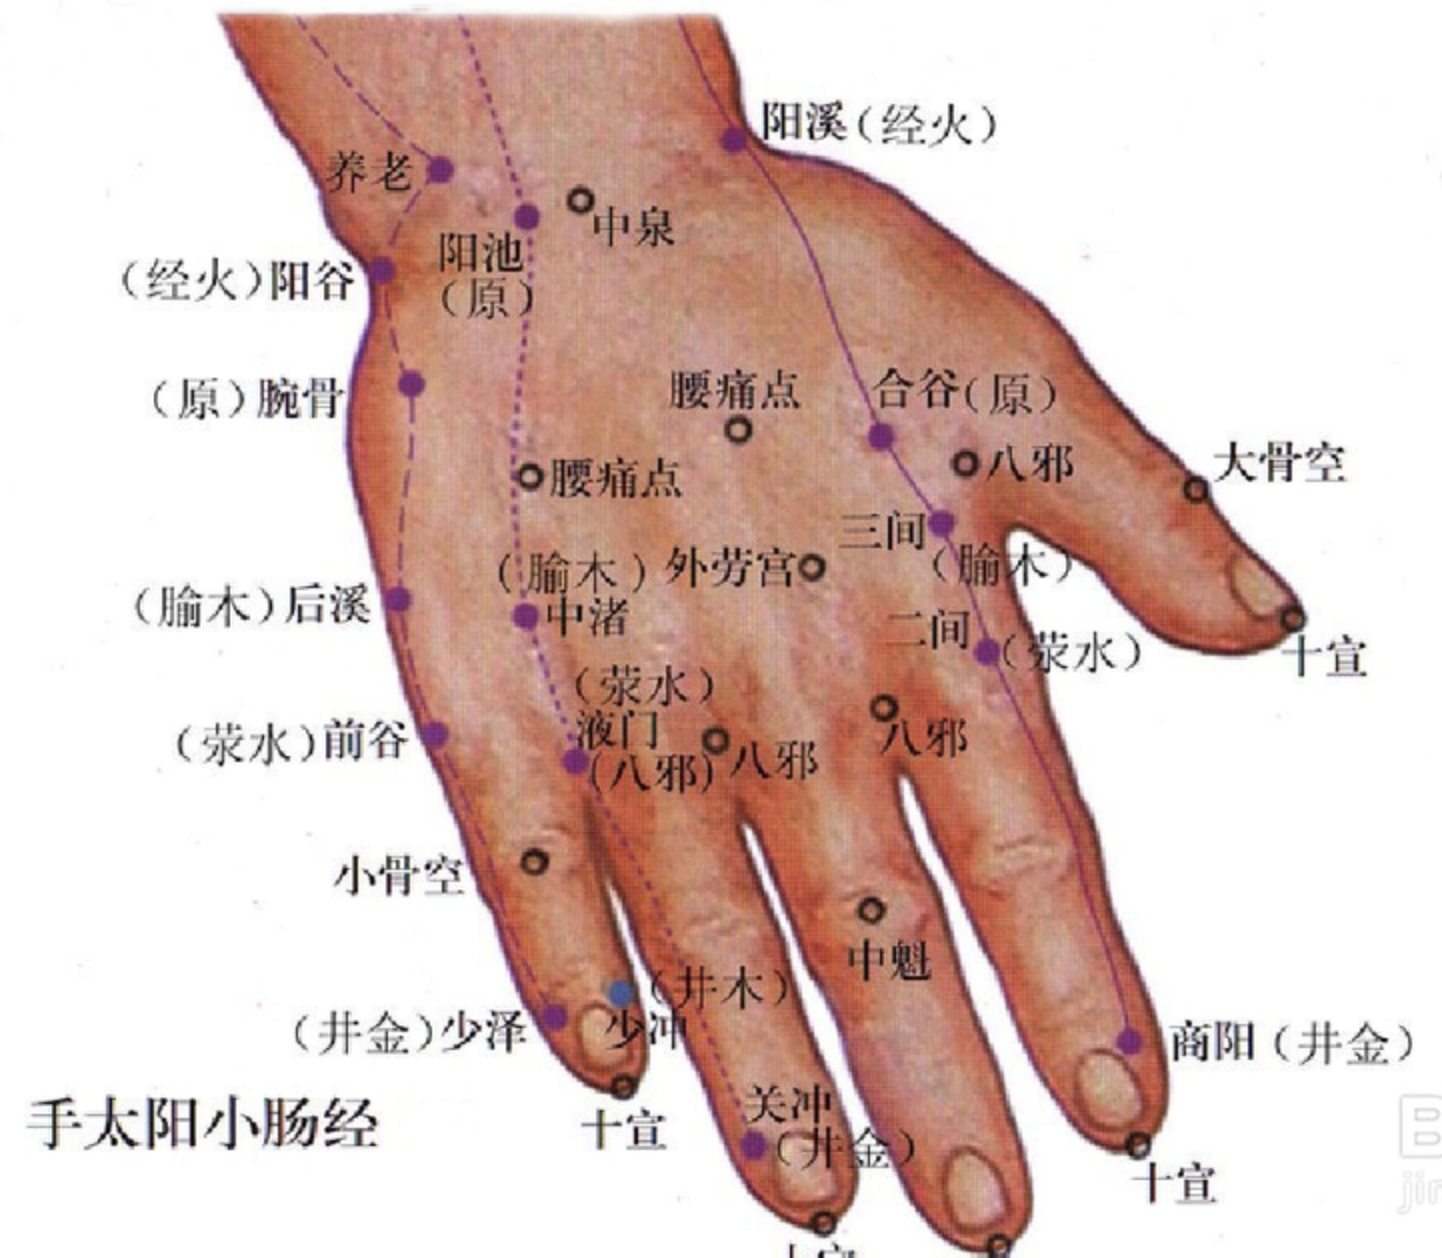

【(六)手太阳小肠经(图10-24-1)】

2、歌诀 手太阳经小肠穴,少则先行小指末,前谷后溪腕骨间,阳谷须同养老列,支正小海上肩贞,臑(nào)俞天宗秉风合,曲垣肩外复肩中,天窗循次上天容,此经穴数一十九,还有颧髎(liáo)入听宫。

3、经脉循行 起于手小指外侧端(少泽),沿手背外侧至腕部直上沿前臂外侧后缘,经尺骨鹰嘴与肱骨内上髁之间,出于肩关节,绕行肩胛部,交于大椎(督脉)向下入缺盆部联络心脏,沿食管过膈达胃,属于小肠。

缺盆部支脉:沿颈部上达面颊,至目外眦(zì),转入耳中(听宫)。

颊部支脉:上行目眶下,抵于鼻旁,至目内眦(睛明)、交于足太阳膀胱经。

4、主要病候 少腹痛、腰脊痛引睾丸、耳聋、目黄、颊肿、咽喉肿痛、肩臂外侧后缘痛等。

5、主治概要 主治头、项、耳、目、喉咽病、热病、神志病及经脉循行部位的其他病证。

少泽

【定位】 在小指末节尺侧,距指甲角 0.1 寸(图 10-24-2)。

【主治】 头痛,目翳,咽喉肿痛,乳痈,乳汁少,昏迷,热病。

【配伍】 配膻中、乳根治乳汁少、乳痈。

【刺灸法】 浅刺 0.1 寸或点刺出血。

【附注】 手太阳经所出为“井”。

后溪

【定位】 在手掌尺侧,微握拳,当小指本节(第 5 指掌关节)后的远侧掌横纹头赤白肉际。

【主治】 头项强痛,目赤,耳聋,咽喉肿痛,腰背痛,癫狂痫,疟疾,手指及肘臂挛痛。

【配伍】 配列缺、悬钟治头项强痛,配人中治急性腰扭伤。

【刺灸法】 直刺 0.5 ~ 1 寸。

【附注】 手太阳经所注为“输”;八脉交会穴之一,通督脉。

腰痛点

【定位】 在手背侧,当第 2、第 3掌骨及第 4、第 5 掌骨之间,当腕横纹与掌指关节中点处,一侧 2 穴,左右共 4 穴。

【主治】 急性腰扭伤。

【刺灸法】 由两侧项掌中斜刺 0.5 ~ 0.8 寸;可灸。

外劳宫

【定位】 在手背侧,当第 2、第 3掌骨间,指掌关节后约 0.5 寸处。

【主治】 落枕,手臂痛,胃痛。

【刺灸法】 直刺或斜刺 0.5 ~ 0.8 寸。

八邪

【定位】 在手背侧,微握拳,第 1 至第 5 指间,指蹼缘后方赤白肉际处,左右共 8 穴。

【主治】 手背肿痛,手指麻木,烦热,目痛,毒蛇咬伤。

【刺灸法】 斜刺 0.5 ~ 0.8 寸,或点刺出血。

十宣

【定位】 在手十指尖端,距指甲游离缘 0.1 寸(指寸),左右共 10 穴(图10-36)。

【主治】 昏迷,癫痫,高热、咽喉肿痛。

【刺灸法】 浅刺 0.1 ~ 0.2 寸,或点刺出血。